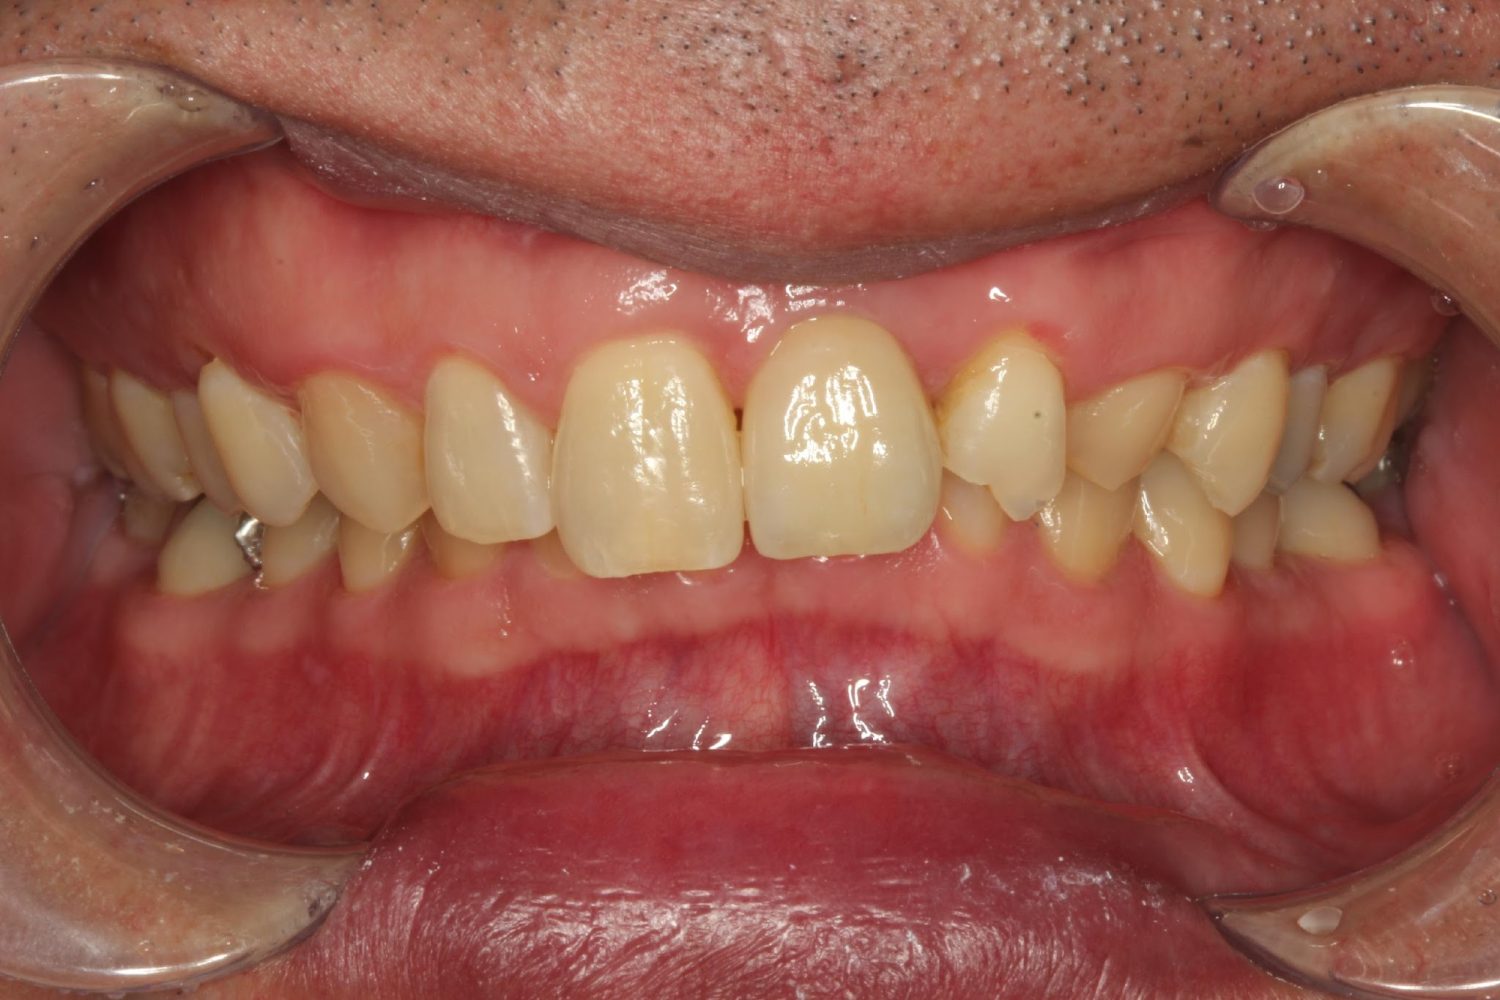

インプラント治療の症例紹介⑨

Before

After

主訴

前歯が揺れる、咬むと痛い

治療内容

抜歯後骨造成手術を行い、その後インプラント埋入手術を行いました。

治療費

462,000円(税込)

治療期間

7ヶ月

通院回数

15回

想定されたリスク

※経年的な歯肉退縮の恐れ.インプラント周囲炎の恐れがありました。

外傷により歯根破折を生じたケース。骨欠損が大きかったので骨造成術を行い、審美ゾーンにインプラント補綴を行った症例です。